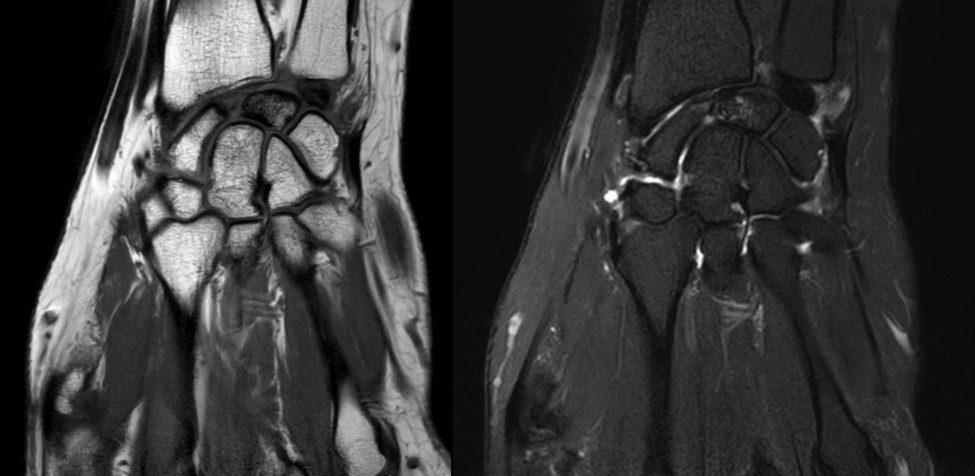

Here, we present two cases of Kienböck’s disease classified as Lichtman stage IIIc, characterized by complete osteonecrosis and a coronal fracture of the lunate, without associated cartilage damage. Both patients underwent a medial closing wedge osteotomy of the radius combined with compression screw fixation of the lunate fracture. The two patients were female, aged 42 and 47 years, with a history of wrist pain. Pre-operative imaging included standard wrist radiography, which revealed a negative ulnar variance (radiographic ulnar index), computed tomography (CT) confirming the presence of a lunate fracture, and MRI demonstrating osteonecrosis (showing a hypointense signal on T1-weighted sequences and a hyperintense signal on T2-weighted sequences, with no gadolinium enhancement). No signs of carpal instability or cartilage degeneration were observed in the surrounding structures.

- Patient A: A 42-year-old right-handed housewife presented with significant pain and stiffness in her dominant wrist persisting for 4 months. She had no history of trauma and was a non-smoker. Her medical history was notable for diabetes and a prior episode of deep vein thrombosis in the lower limb several years earlier (Fig. 1, 2, 3).

Figure 2: Computed tomography scan.

Figure 3: Magnetic resonance imaging.

Figure 5: Computed tomography scan.

Figure 6: Magnetic resonance imaging.